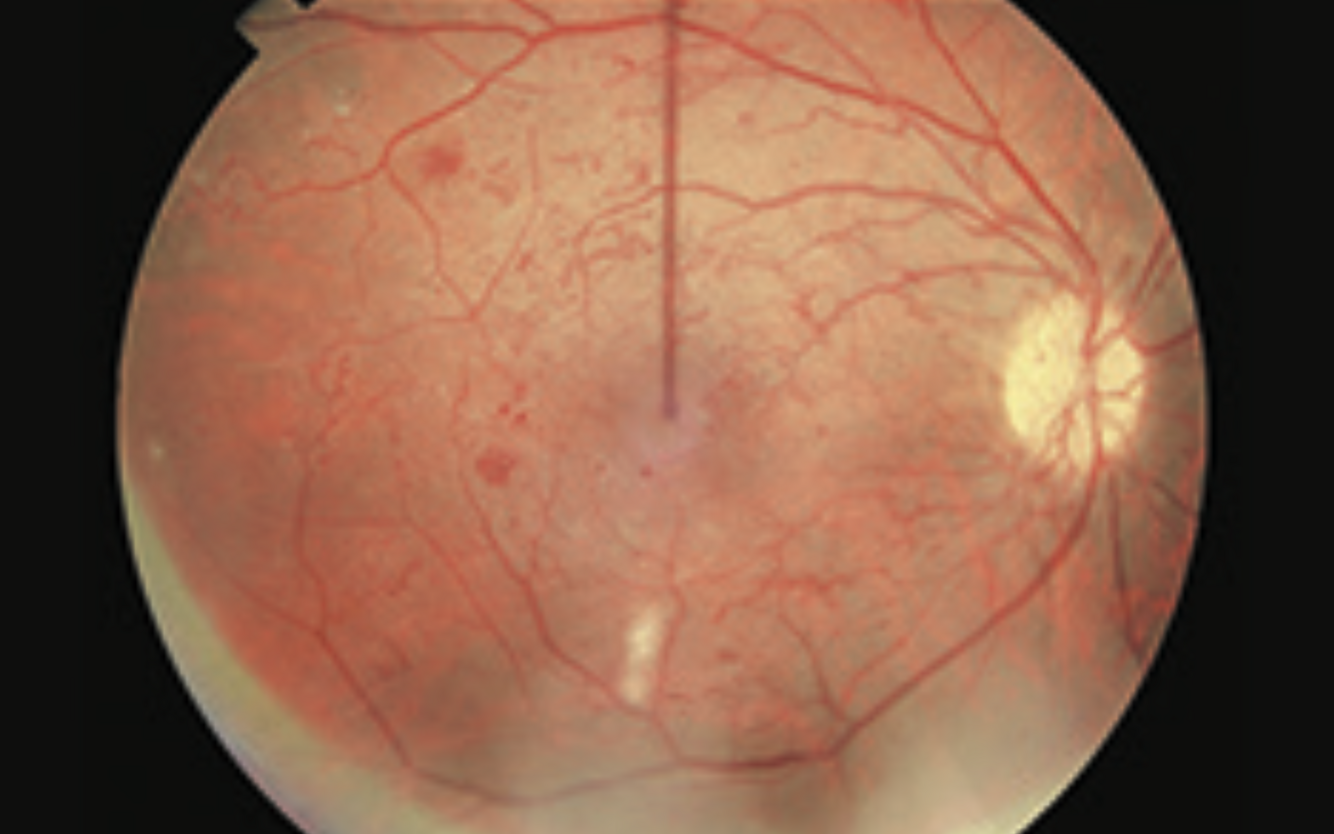

Diabetic Maculopathy

- hard exudates in macular area

- flame haemorrhages and microaneurysms